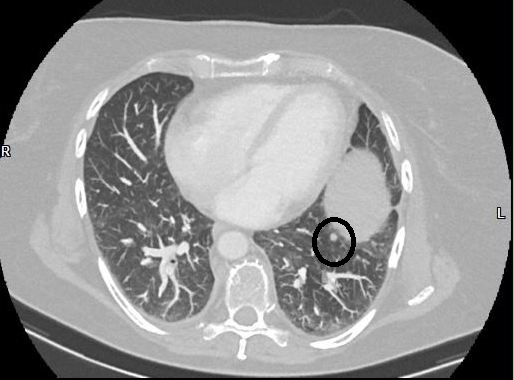

Ich habe schon einen beachtlichen Stapel voller CDs mit Bildern von allen möglichen meiner Körperteilen, aber erst jetzt bekomme ich das kleine Böse so gezeigt, dass ich es zu Hause auch wiederfinden kann. Die kleinere und einzige eindeutige Metastase ist hier zu sehen. Ziemlich genau in der horizontalen Mitte des Bildes am unteren linken Rand der Eiform, die aus dieser Sicht mitten im Lungenflügel gebettet scheint, aber nur schon den Beginn des Zwerchfells darstellt, sitzt diese winzig kleine runde Form. also hier:

Wenn ich meinen Blick endlich von dem kleinen tanzenden Figürchen abwenden kann, das da unten im linken Lungenflügel (also in Wirklichkeit im rechten, aber ich will jetzt mal nicht kleinlich sein) mit gesenktem Kopf herumgeistert, frappiert mich die Winzigkeit dieser Erbse, etwa 5 mm heißt es. Seine wohlgeformte Rundheit zeichnet es als eindeutige Metastase aus, im Gegensatz zu allen anderen Veränderungen, die, wie es mir bei Radiologen öfters passiert, nur schriftliche Metastasen sind, im trauten Gespräch eher nicht. Dieses eine Pünktchen ist also die Ursache all der neuerlichen Aufregung. Unscheinbar trifft es am besten. Es blinkt nicht grellrot auf, es pulsiert nicht, nix. Und es wächst nicht, das ist die gute Nachricht.

Dieses flache Schwarz-Weiß der CT-Bilder hilft beim Verständnis der Krankheit nicht weiter. So wie ich die tödliche Gefahr nicht in diesem kleinen Kreis erkennen kann, genau so kann ich diese farblosen Schnitte nicht mit meinem Körperinneren zusammenbringen. Es führt kein Weg von diesem Bild zu einem Gefühl für den Krebs, es ist mir nach all den Jahren nicht gelungen, ein Gespür dafür zu entwickeln und auch die „Schnitte“, also Querschnitte durch meinen Oberkörper bringen mich am Ende nicht weiter. Ich bleibe lieber beim Bild von der kleinen grünen Erbse. Wobei es jetzt aber doch geholfen hat, ist bei der Beruhigung. Das rote Blut und kratzige schwarze Gekröse ist wieder gewichen zugunsten dieser neutralen Flachheit.

OH MY GOSH! (das sagt man an Stelle von „Oh my God“, wenn man aus der Kirche ausgetreten ist ;-)) Es ist natürlich von Bedeutung, dass diese Bilder seitenverkehrt sind. Natürlich spüre ich diese Stelle, ich weiß auch genau, wo sie sich befindet, nämlich dort, wo ich den Krebs lokalisieren würde, wenn ich mich nicht erst gedanklich auf die Reise des wo-war-das-jetzt-wieder-ach-ja-der-ursprungskrebs-sitzt-in-der-rechten-brust begebe, sondern einfach spontan auf die Stelle zeigen müsste, wo er sitzt:

Darf ich vorstellen: Meine Mitte, einmal durchgeschnitten, wie wenn die Fleischfachverkäuferin eine Scheibe Schinken abschneidet. Das ist das Zentrum der Zerstörung, dort suppten die anderthalb Liter Pleurawasser vor sich hin, dort saß die schlimmste aller Entzündungen vom gruseligen Drainage-Schlauch. Klar. Und jetzt sehe ich auch, wie das kleine tanzende Figürchen sich dorthin neigt. Klasse, da ist das Thema fürs nächste Aquarell.